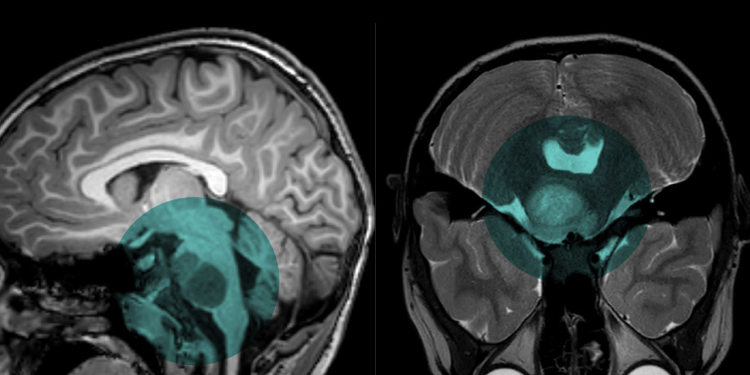

Um adolescente belga de 13 anos entrou para a história da medicina em 2024 ao se tornar o primeiro paciente do mundo considerado curado de um dos cânceres infantis mais agressivos já registrados: o glioma pontino intrínseco difuso (DIPG). O caso é tratado por especialistas como um marco científico no combate a tumores cerebrais pediátricos.

Lucas Jemeljanova foi diagnosticado aos 6 anos com o tumor, localizado no tronco cerebral — área vital responsável por funções como respiração e batimentos cardíacos. À época, os médicos informaram à família que ele provavelmente teria menos de um ano de vida.

O DIPG é raro, afeta principalmente crianças entre 4 e 6 anos e é considerado praticamente fatal. Menos de 10% dos pacientes sobrevivem por mais de dois anos após o diagnóstico. Até então, nunca havia sido registrada uma cura da doença.

O DIPG cresce rapidamente e atinge áreas extremamente delicadas do cérebro, o que dificulta cirurgias. Tratamentos convencionais, como quimioterapia e radioterapia, historicamente apresentaram resultados limitados.